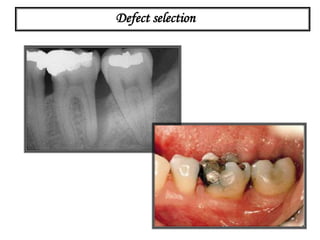

Defect selection

A sulcular incision full thickness flap is reflected. A three wall

intrabony defect is visualized at the distal of the first molar.